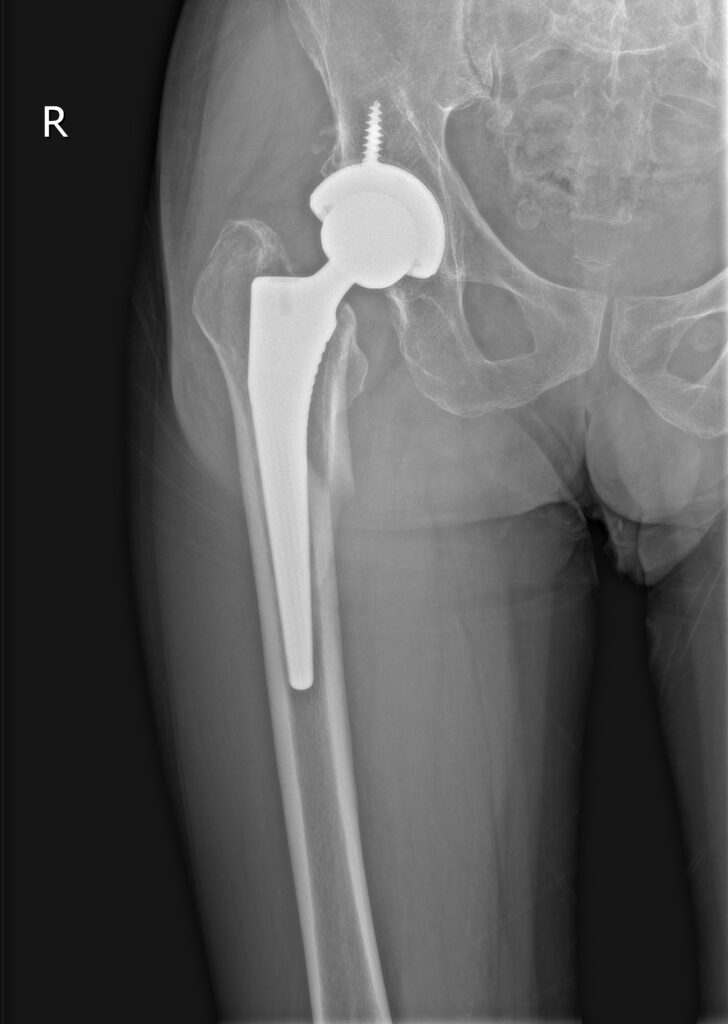

全髋术后股骨侧假体周围骨折切开复位内固定股骨柄翻修术(Open reduction, internal fixation and femoral stem revision for periprosthetic fractures on the femoral side after total hip surgery)